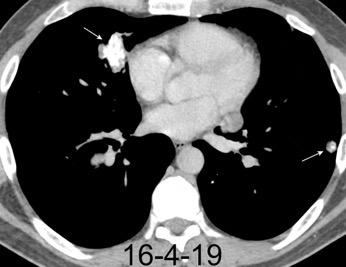

Edema cardiogénico

10% de los pacientes con edema pulmonar

Presión vascular elevada en el pulmón.

“Hidrostático”

Ocurre con fallo rápido. Insuficiencia mitral aguda post IAM, Endocarditis séptica.